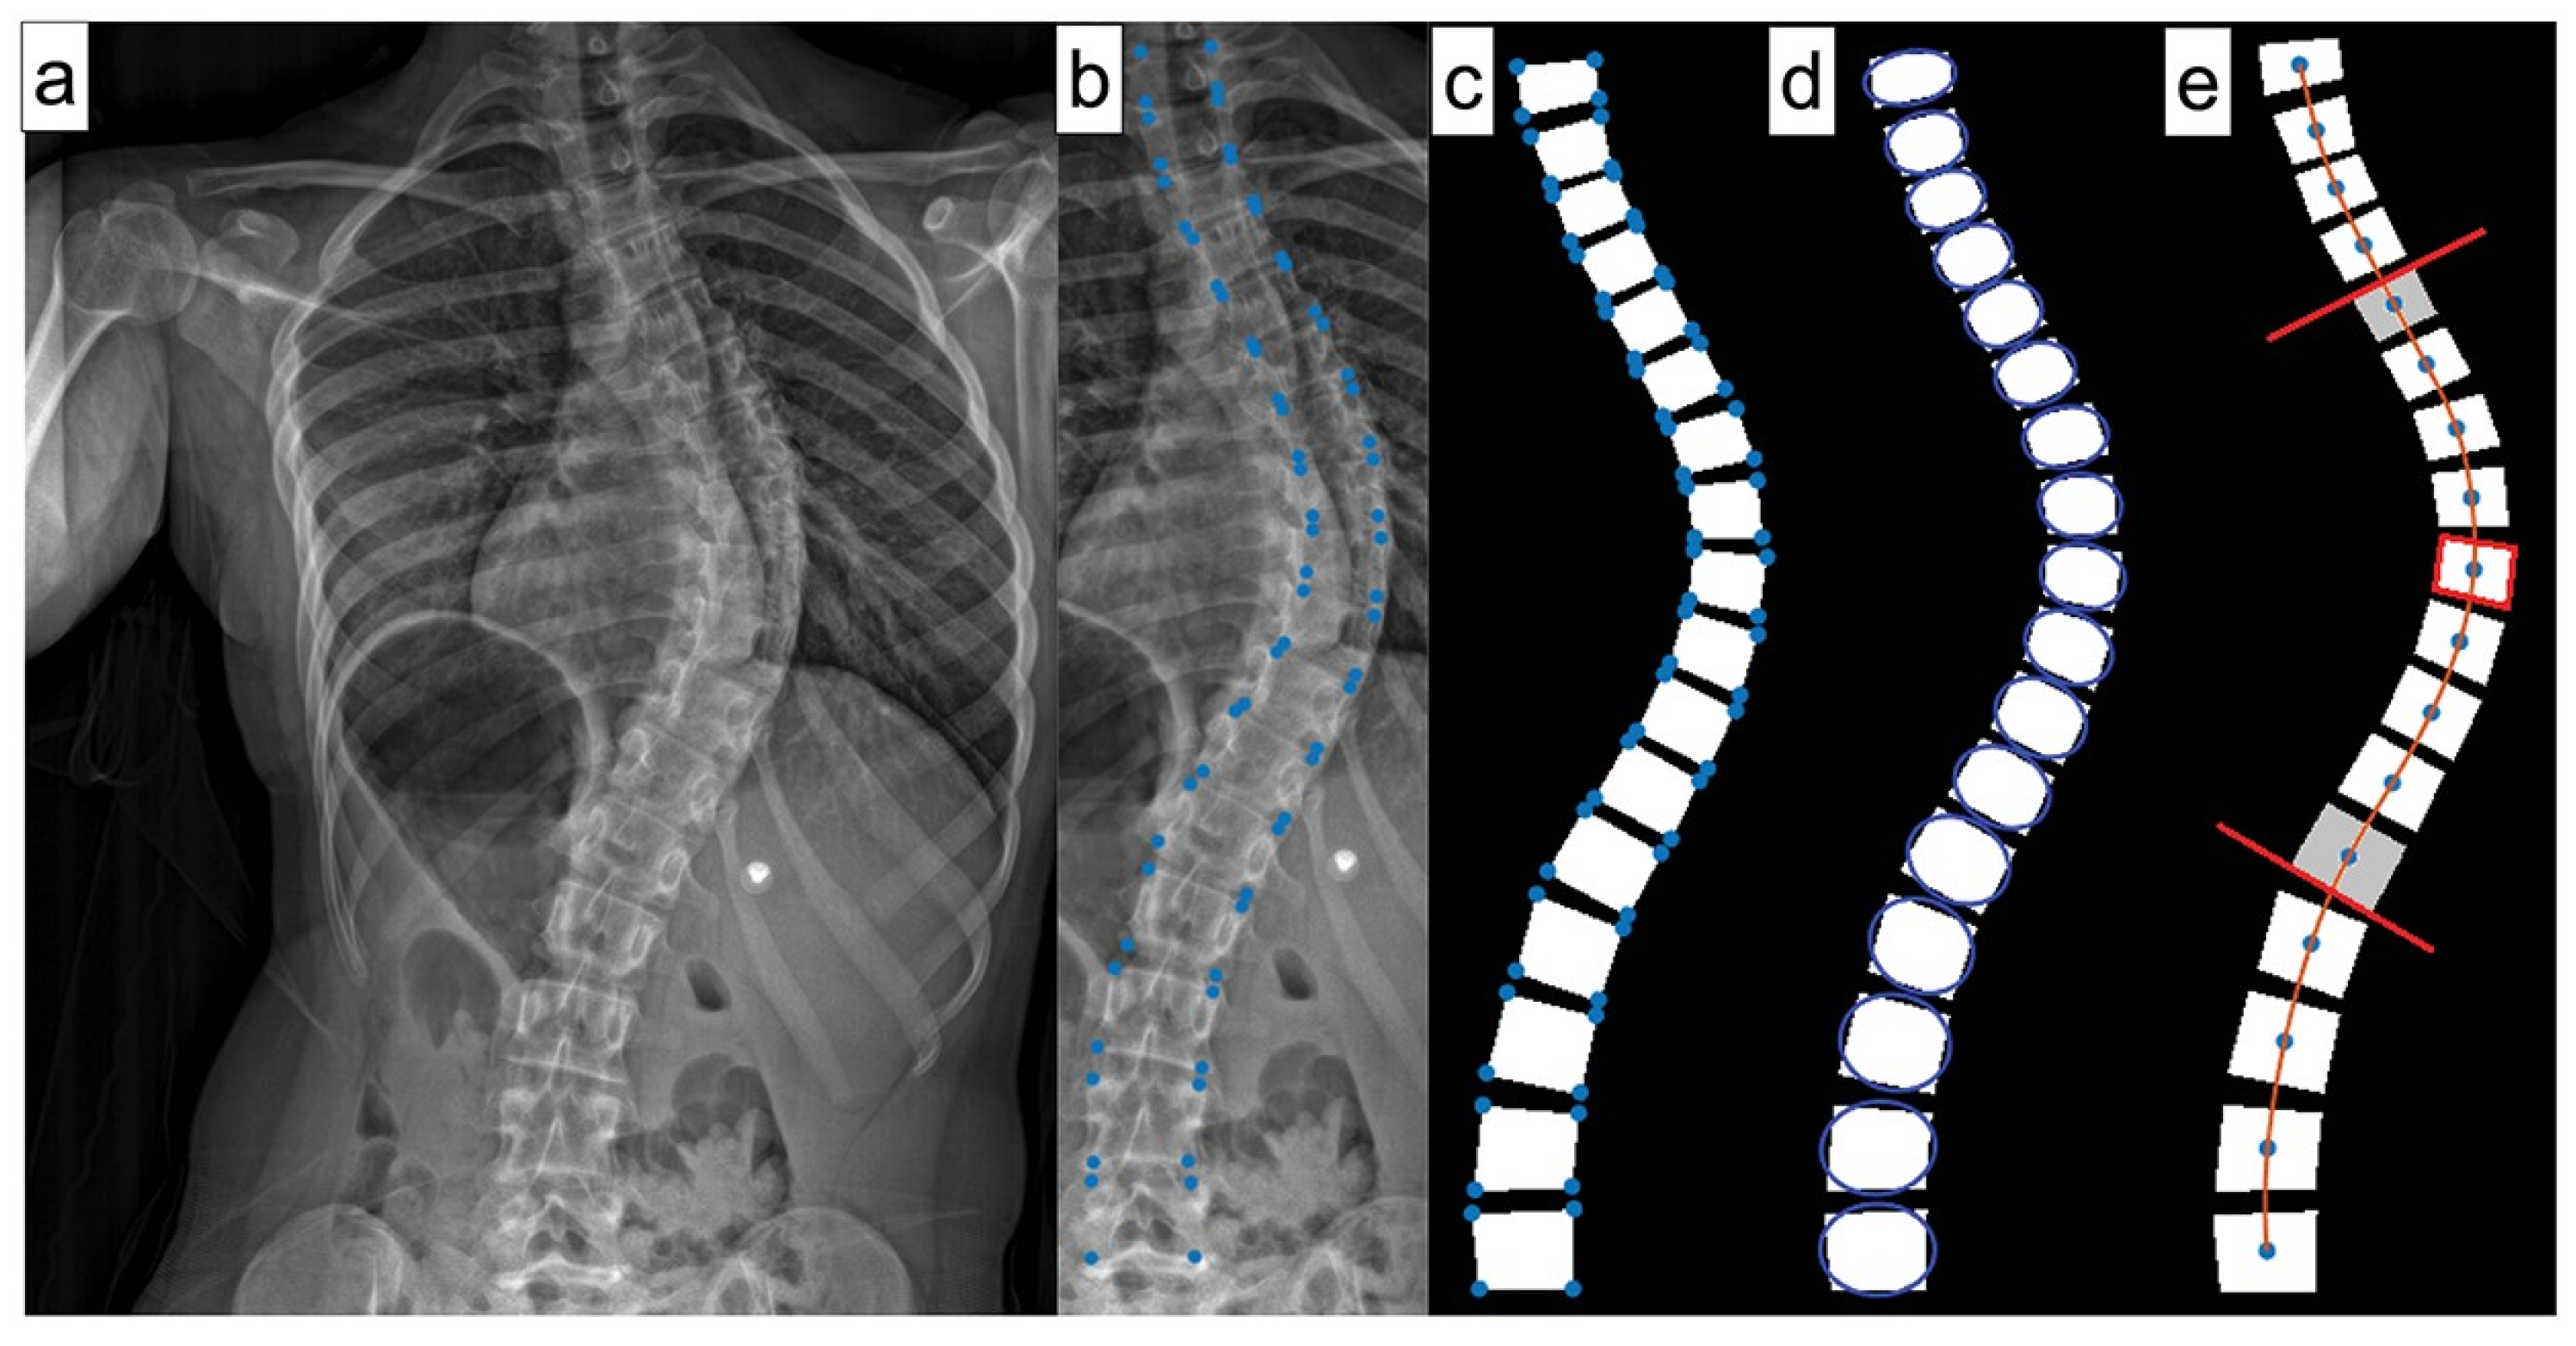

ML can also effectively forecast spinal curve progression, aiding in timely intervention decisions. Using features like initial Cobb angle (

Figure 6) and Risser stage, a Random Forest model has been shown to be able to predict final Cobb angles in 193 AIS patients from a single center with a 4.64° mean absolute error [

15]. Multiple models have also been developed to help identify screw brands, which is helpful for preoperative planning in revision spine surgeries [